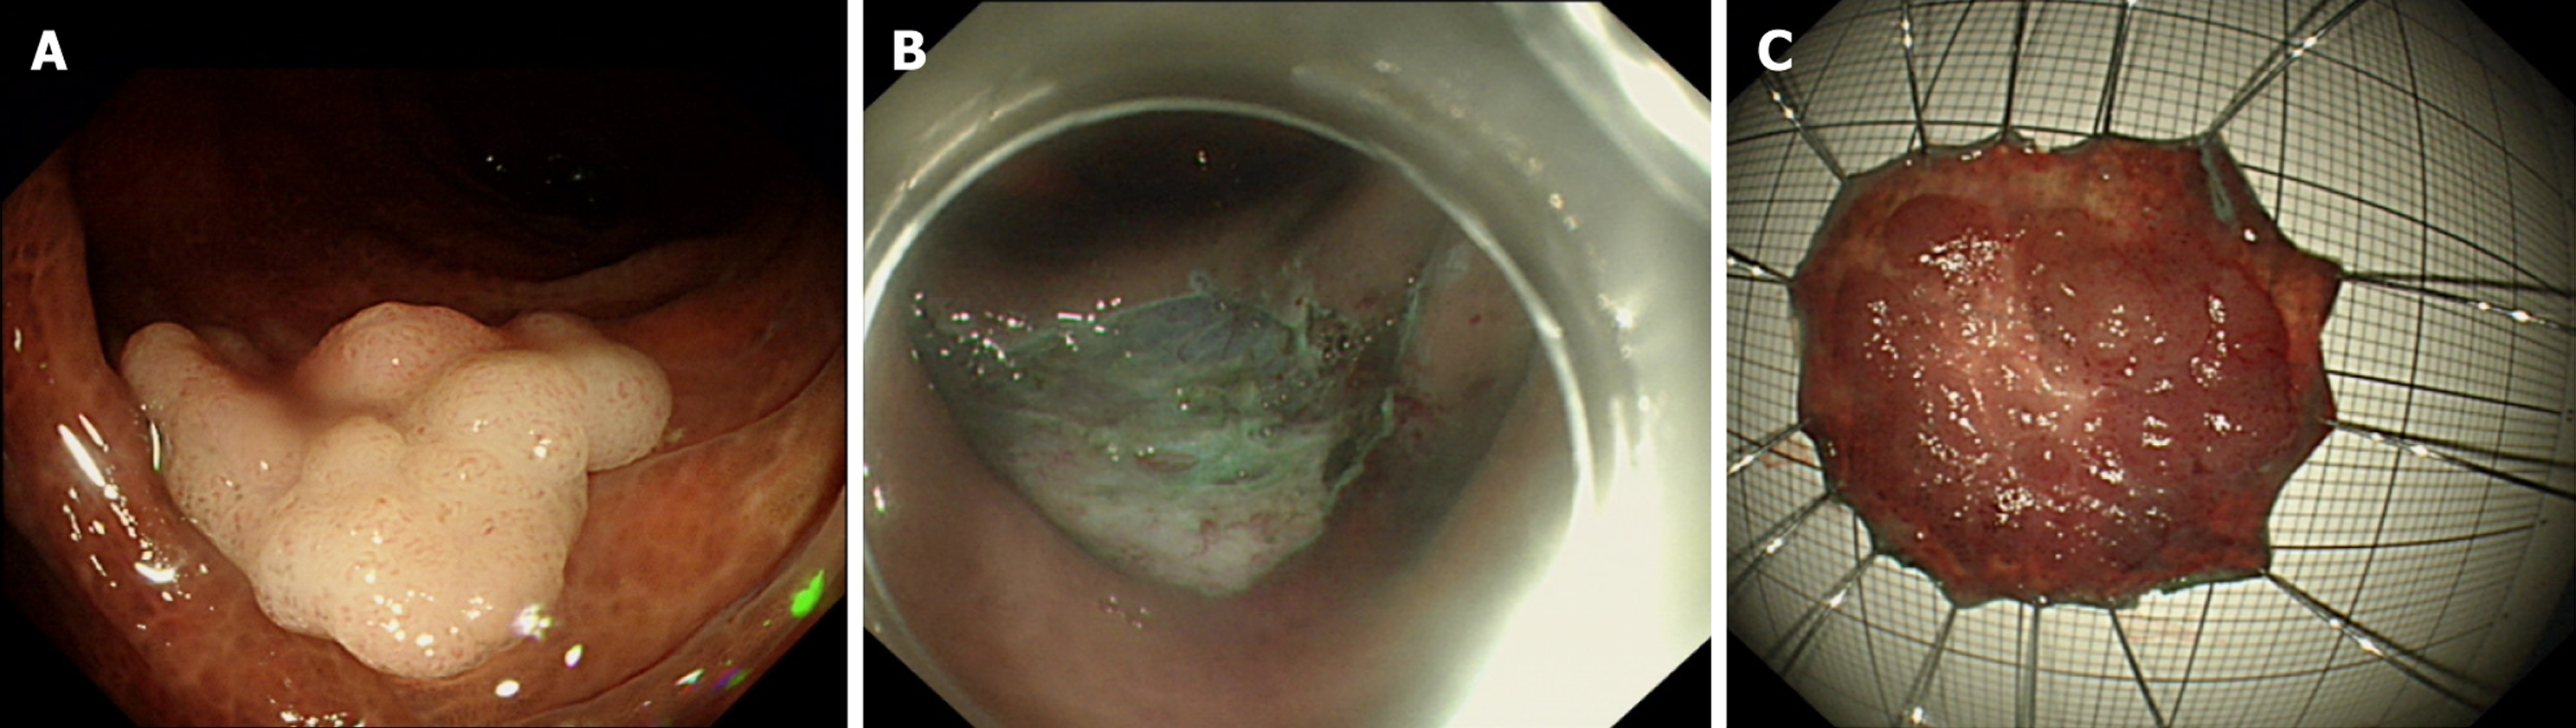

Figure 1 Endoscopic views during endoscopic submucosal dissection.

A: Preoperative lesion; B: Post-endoscopic submucosal dissection mucosal defect; C: Resected specimen.